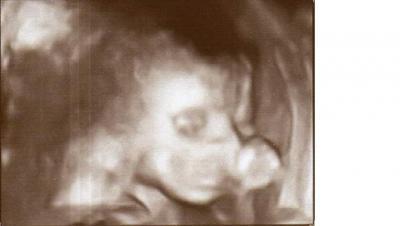

war gestern zum großen US und hab meinen Paps mitgenommen da mein Mann arbeiten musste. Unser kleiner Kerl war sowas von aktiv, hat den FA ganz schön auf Trab gehalten und mit allen vieren ausgeteilt. Zwischendurch immer eine Pause mit Daumen im Mund. Zu süß. Mein Paps war total begeistert, der kleine ist rundum fit und ich schwebe auf einer rosa Wolke. Man konnte sogar die Herzkammern, Vorhöfe und Herzklappen erkennen. Dann hat der FA sogar auf 4D umgeschaltet. Und nach langer geduldiger Suche einen tollen Schnappschuss machen. Darf ich vorstellen: unser Tobias :-)

Bild zu wir bekommen einen Daumenlutscher ;-) - Forum für Oktober - Mamis